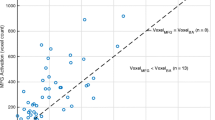

In the study group, language lateralization based on hemispheric LI demonstrated 212 LL and 193 AL patients. Frontal LI demonstrated 217 LL and 188 AL patients. Broca’s LI demonstrated 236 LL and 169 AL patients. Temporal LI demonstrated 222 LL and 183 AL patients. Wernicke’s LI demonstrated 217 LL and 188 AL patients. Laterality results according to tumor type are reported in Table 3. Two representative cases are displayed in Fig. 2. The distribution of the five LIs is presented in Fig. 3. The age distribution of AL and LL patients according to the calculated LIs was not significantly different on Mann–Whitney U test.

Box plots representing the distribution of the five laterality indexes (LI) calculated in the total population of our study: hemispheric LI (a), frontal LI (b), Broca’s LI (c), temporal LI (d), and Wernicke’s LI (e). Hemispheric LI demonstrated 210 left-lateralized (LL) and 195 atypical lateralized (AL) patients. Frontal LI demonstrated 221 LL and 184 AL patients. Broca’s LI demonstrated 234 LL and 171 AL patients. Temporal LI demonstrated 220 LL and 185 AL patients. Wernicke’s LI demonstrated 215 LL and 190 AL patients

In the control group, language lateralization based on hemispheric LI demonstrated 35 LL and 14 AL patients. Frontal LI demonstrated 40 LL and 9 AL patients. Broca’s LI demonstrated 46 LL and 3 AL patients. Temporal LI demonstrated 31 LL and 18 AL patients. Wernicke’s LI demonstrated 41 LL and 8 AL patients. Language laterality results in the control group are summarized in Table 4 and supplementary Figs. 1–5.